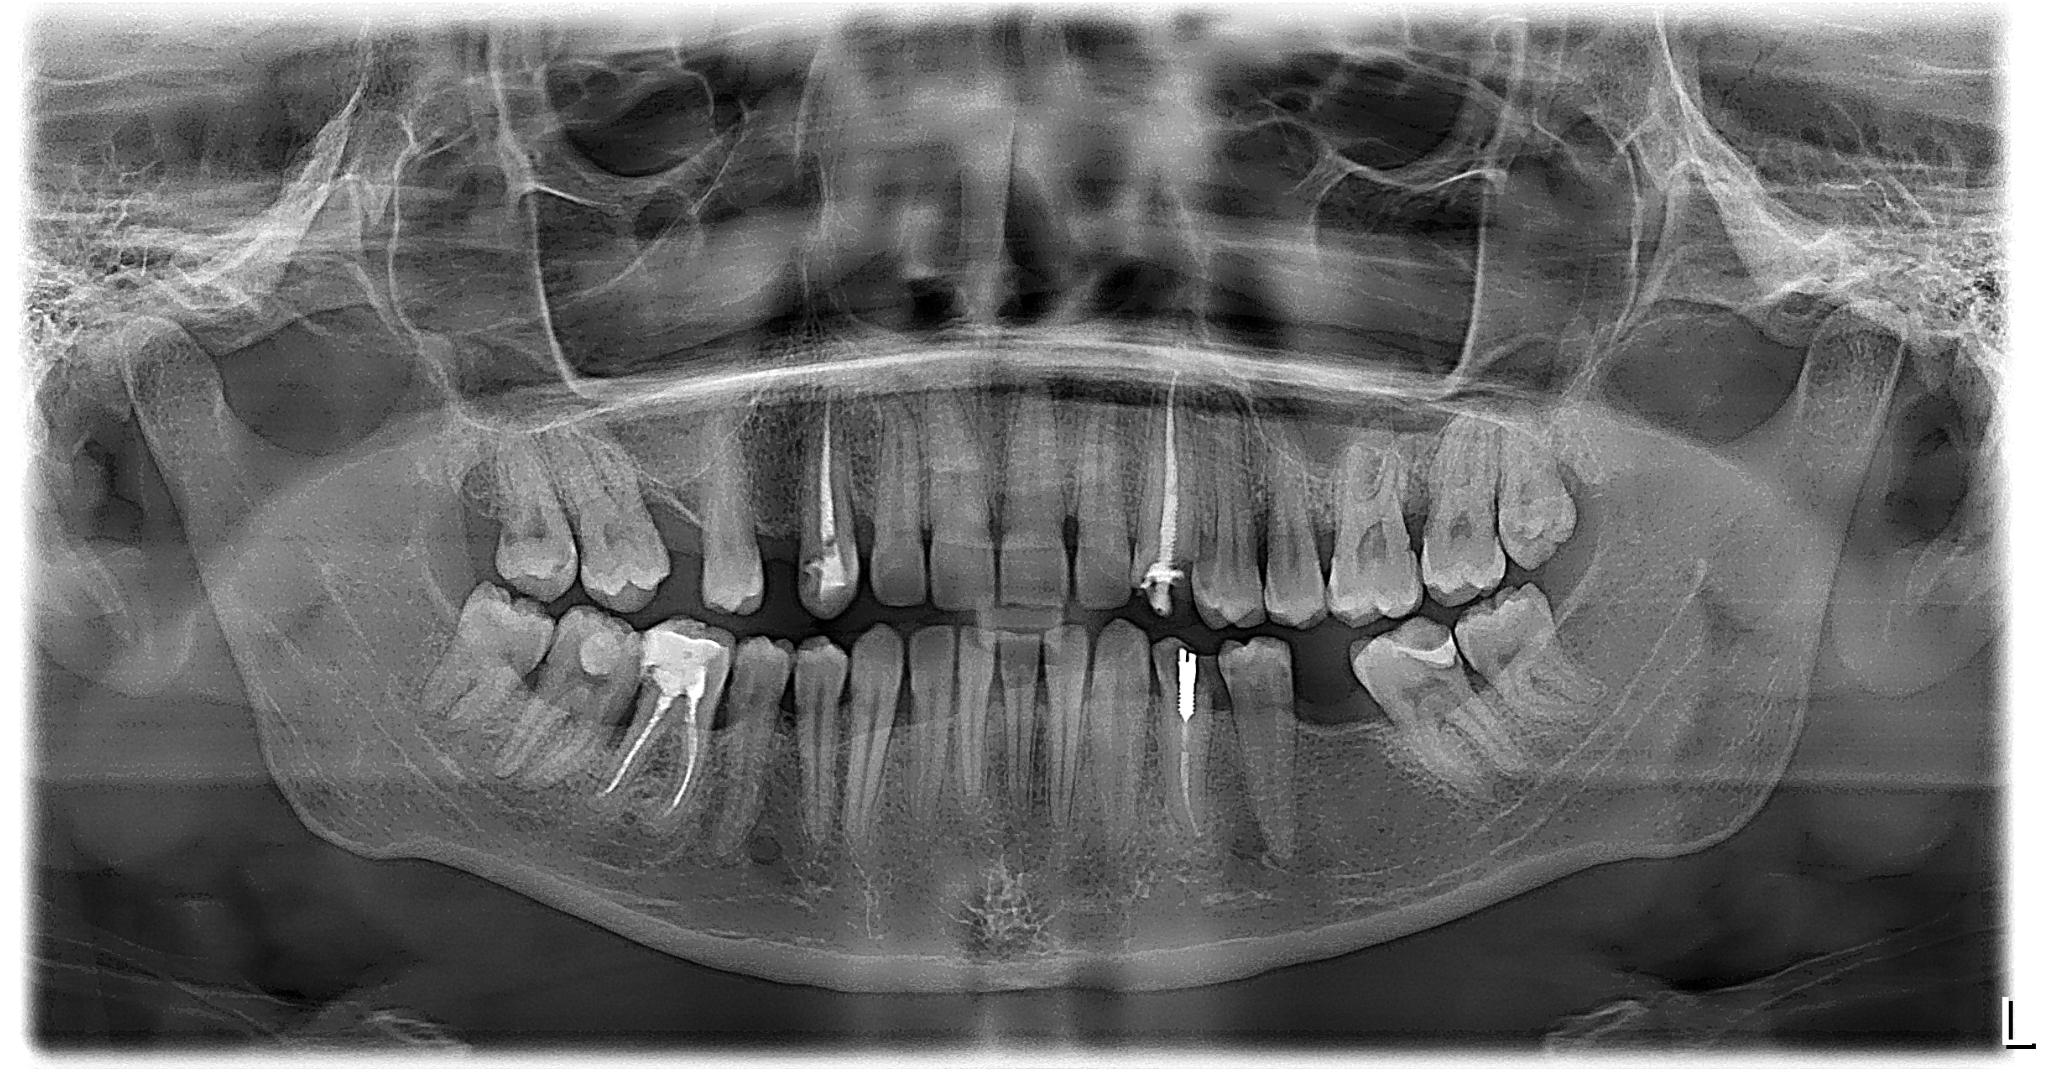

Что вы получаете в итоге? Не просто диск, распечатку или отправку на электронную почту. Вы получаете стопроцентную уверенность. Уверенность в том, что план лечения имплантации составлен идеально, что все каналы будут пройдены до конца, а «зуб мудрости» удалят аккуратно, не задев важные нервы.